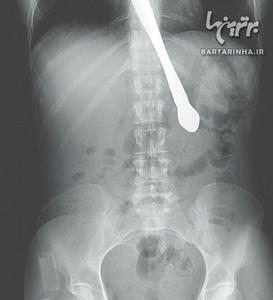

گیر کردن چاقو در مری یک زن

پزشکان از طریق آندوسکوپی چاقو را خارج کرده و اعلام کردند که آسیبی به گلو یا معده این زن وارد نشده است. ...